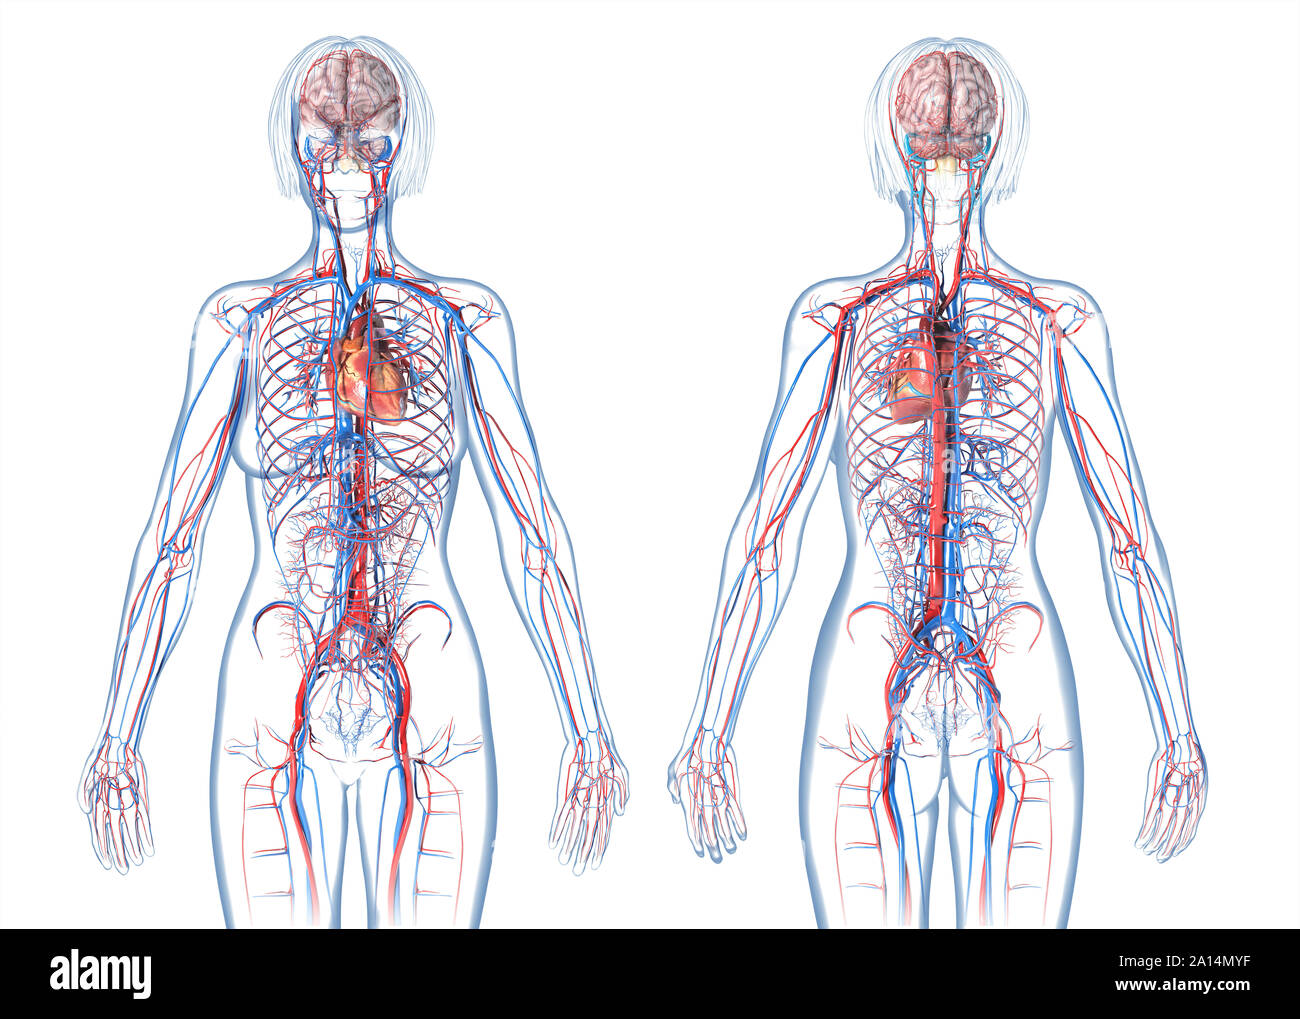

Кровеносная система человека: структура и функции